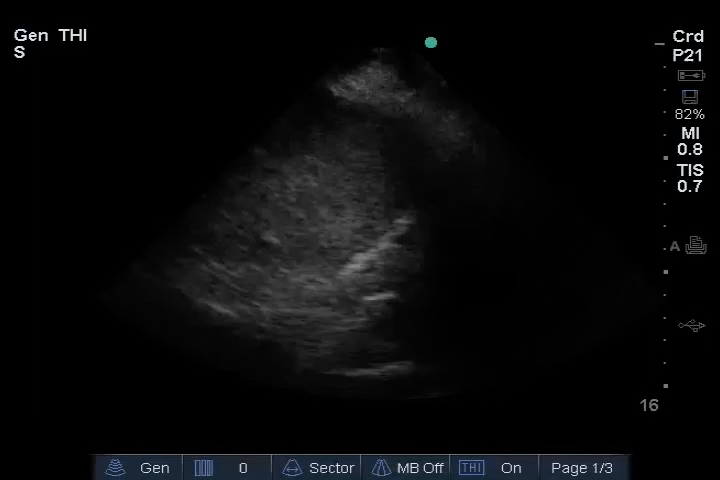

11_Heart_A4CH – LV reduced ejection fraction (EF)